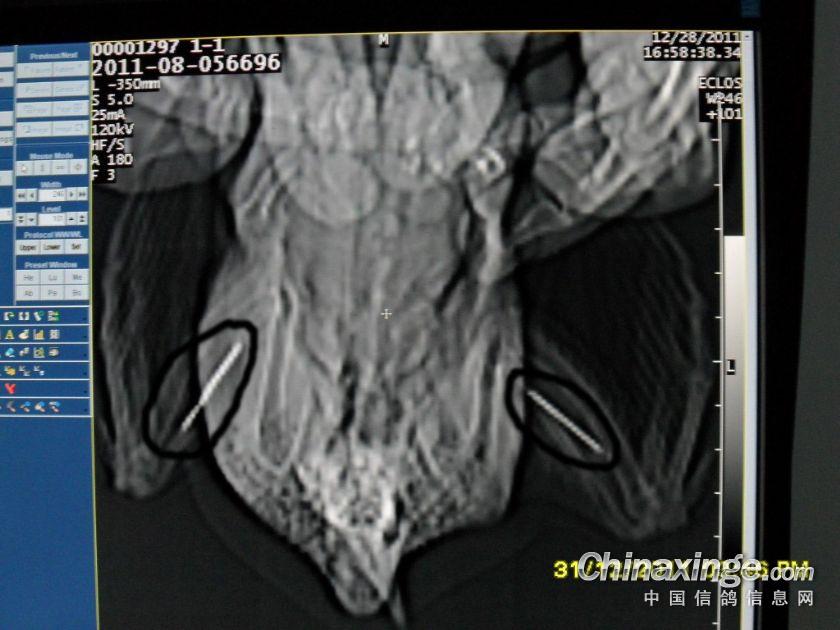

钢针插在翅膀内,翅膀肿胀,开笼后被迫落下!!!

金属物

双侧翅膀的金属物

不同角度的金属物图片